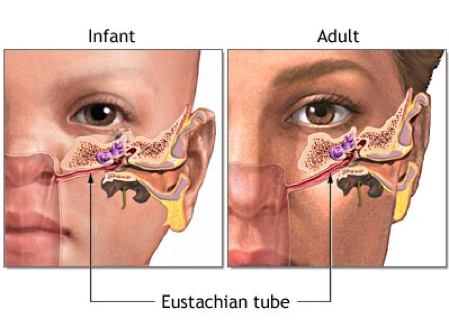

Why are infants more prone to ear infections than adults?

As they have a smaller and more horizontal Eustachian tube –> more direct route for infections to access the tube and therefore the middle ear

As we grow, how does our Eustachian tube change shape?

Becomes more vertical with age